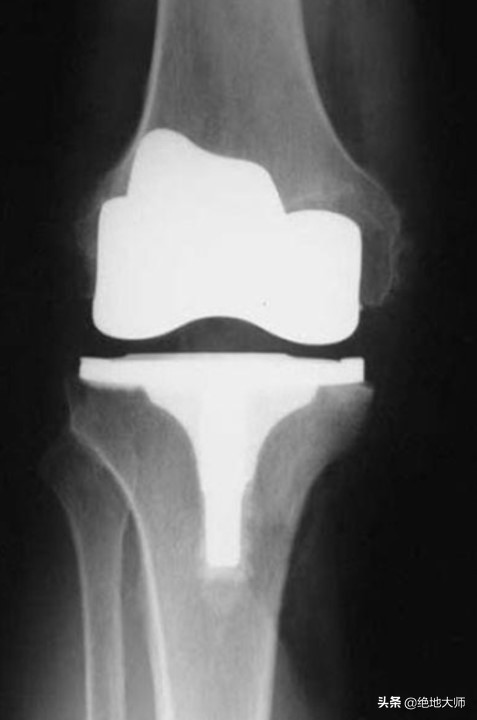

6. POST – POST SURGERY 术后慢性,6m-1y

SCARS ROLE IN POST-SURGERY 术后疤痕作用

FUNCTIONAL PAIN YEARS AFTER SURGICAL INTERVENTION 手术干预后功能性疼痛数年

TIRE WEAR GETS EVEN WORSE YEARS AFTER AUGMENTATION OF THE JOINT POST-POST SURGERY. 在术后关节增强后的几年里,轮胎磨损变得更糟。